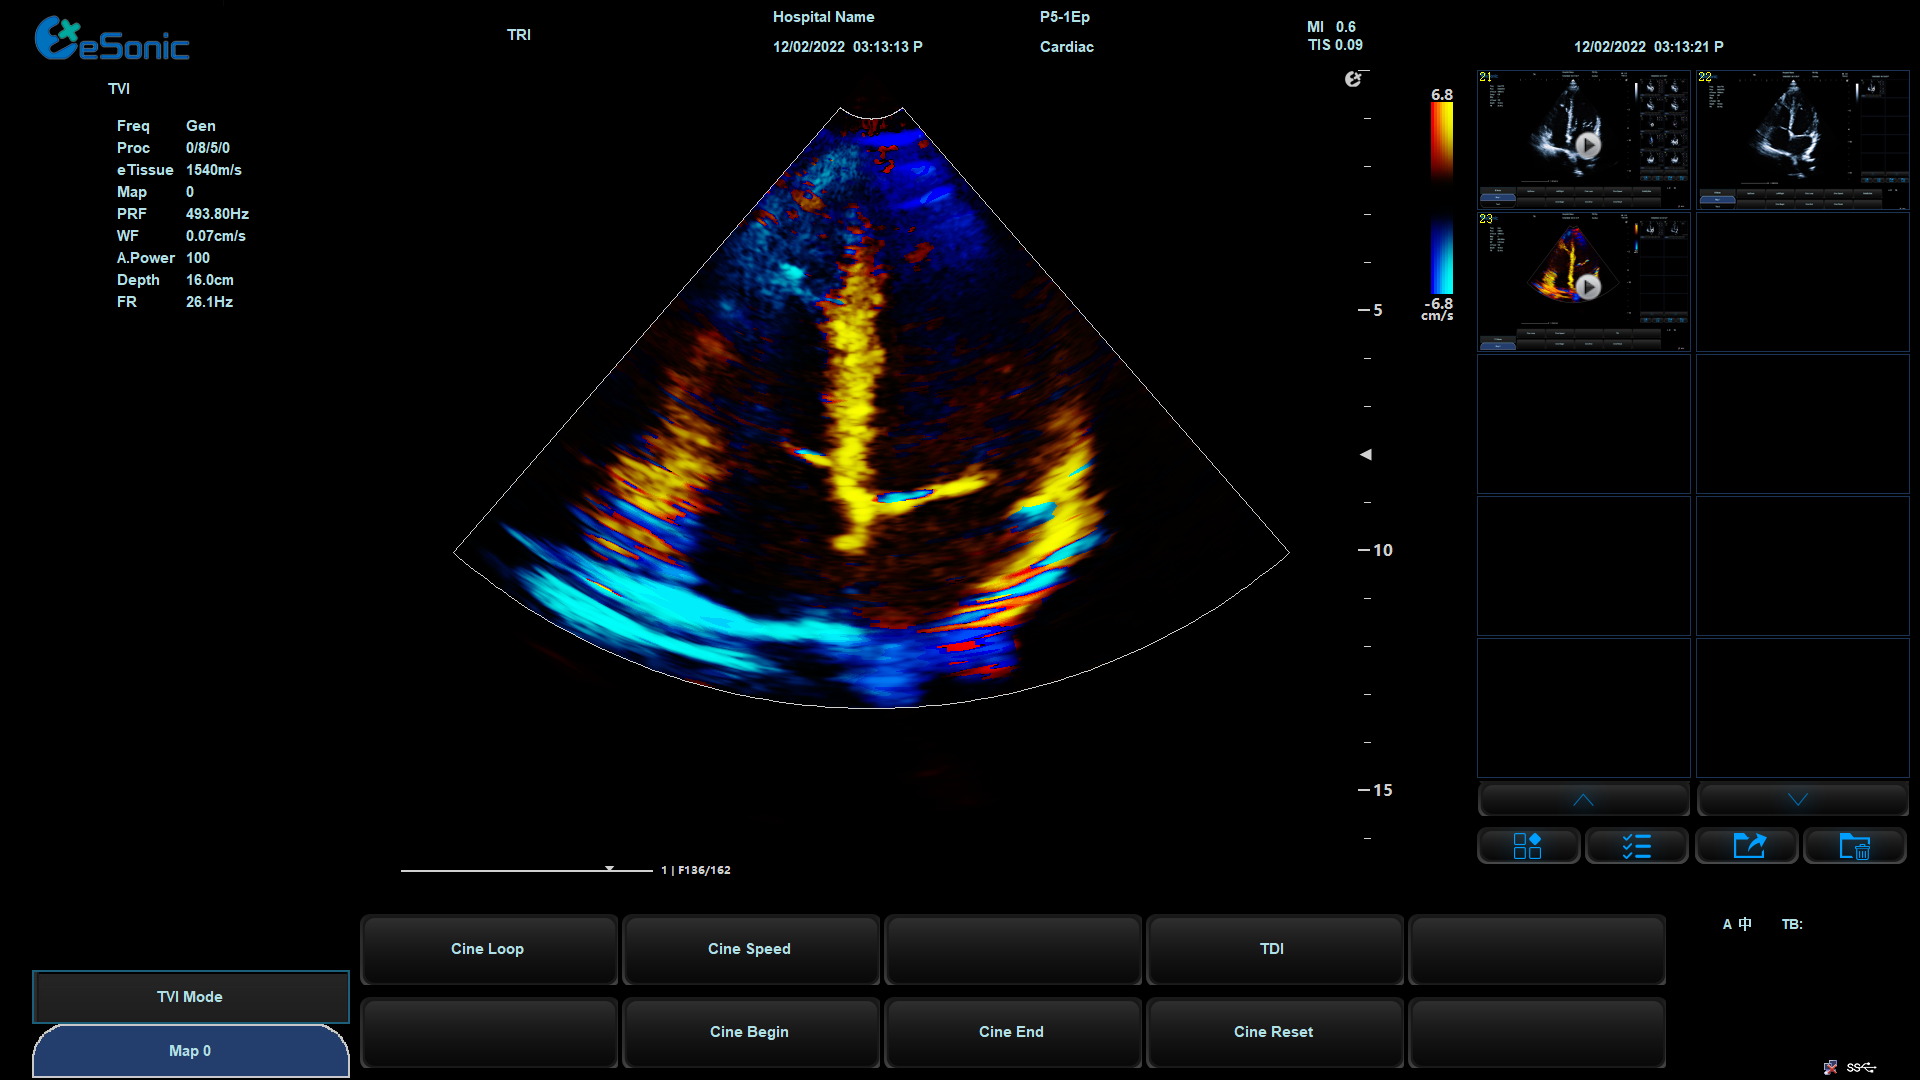

eHertz优异的TDI表现- 图像非常干净

组织多普勒

包含多种模式

可对室壁运动进行速度、加速度的测量和分析

观察心肌运动、定量分析心肌的运动速度变化,检测心肌供血情况

评价早期的舒张功能

image.png